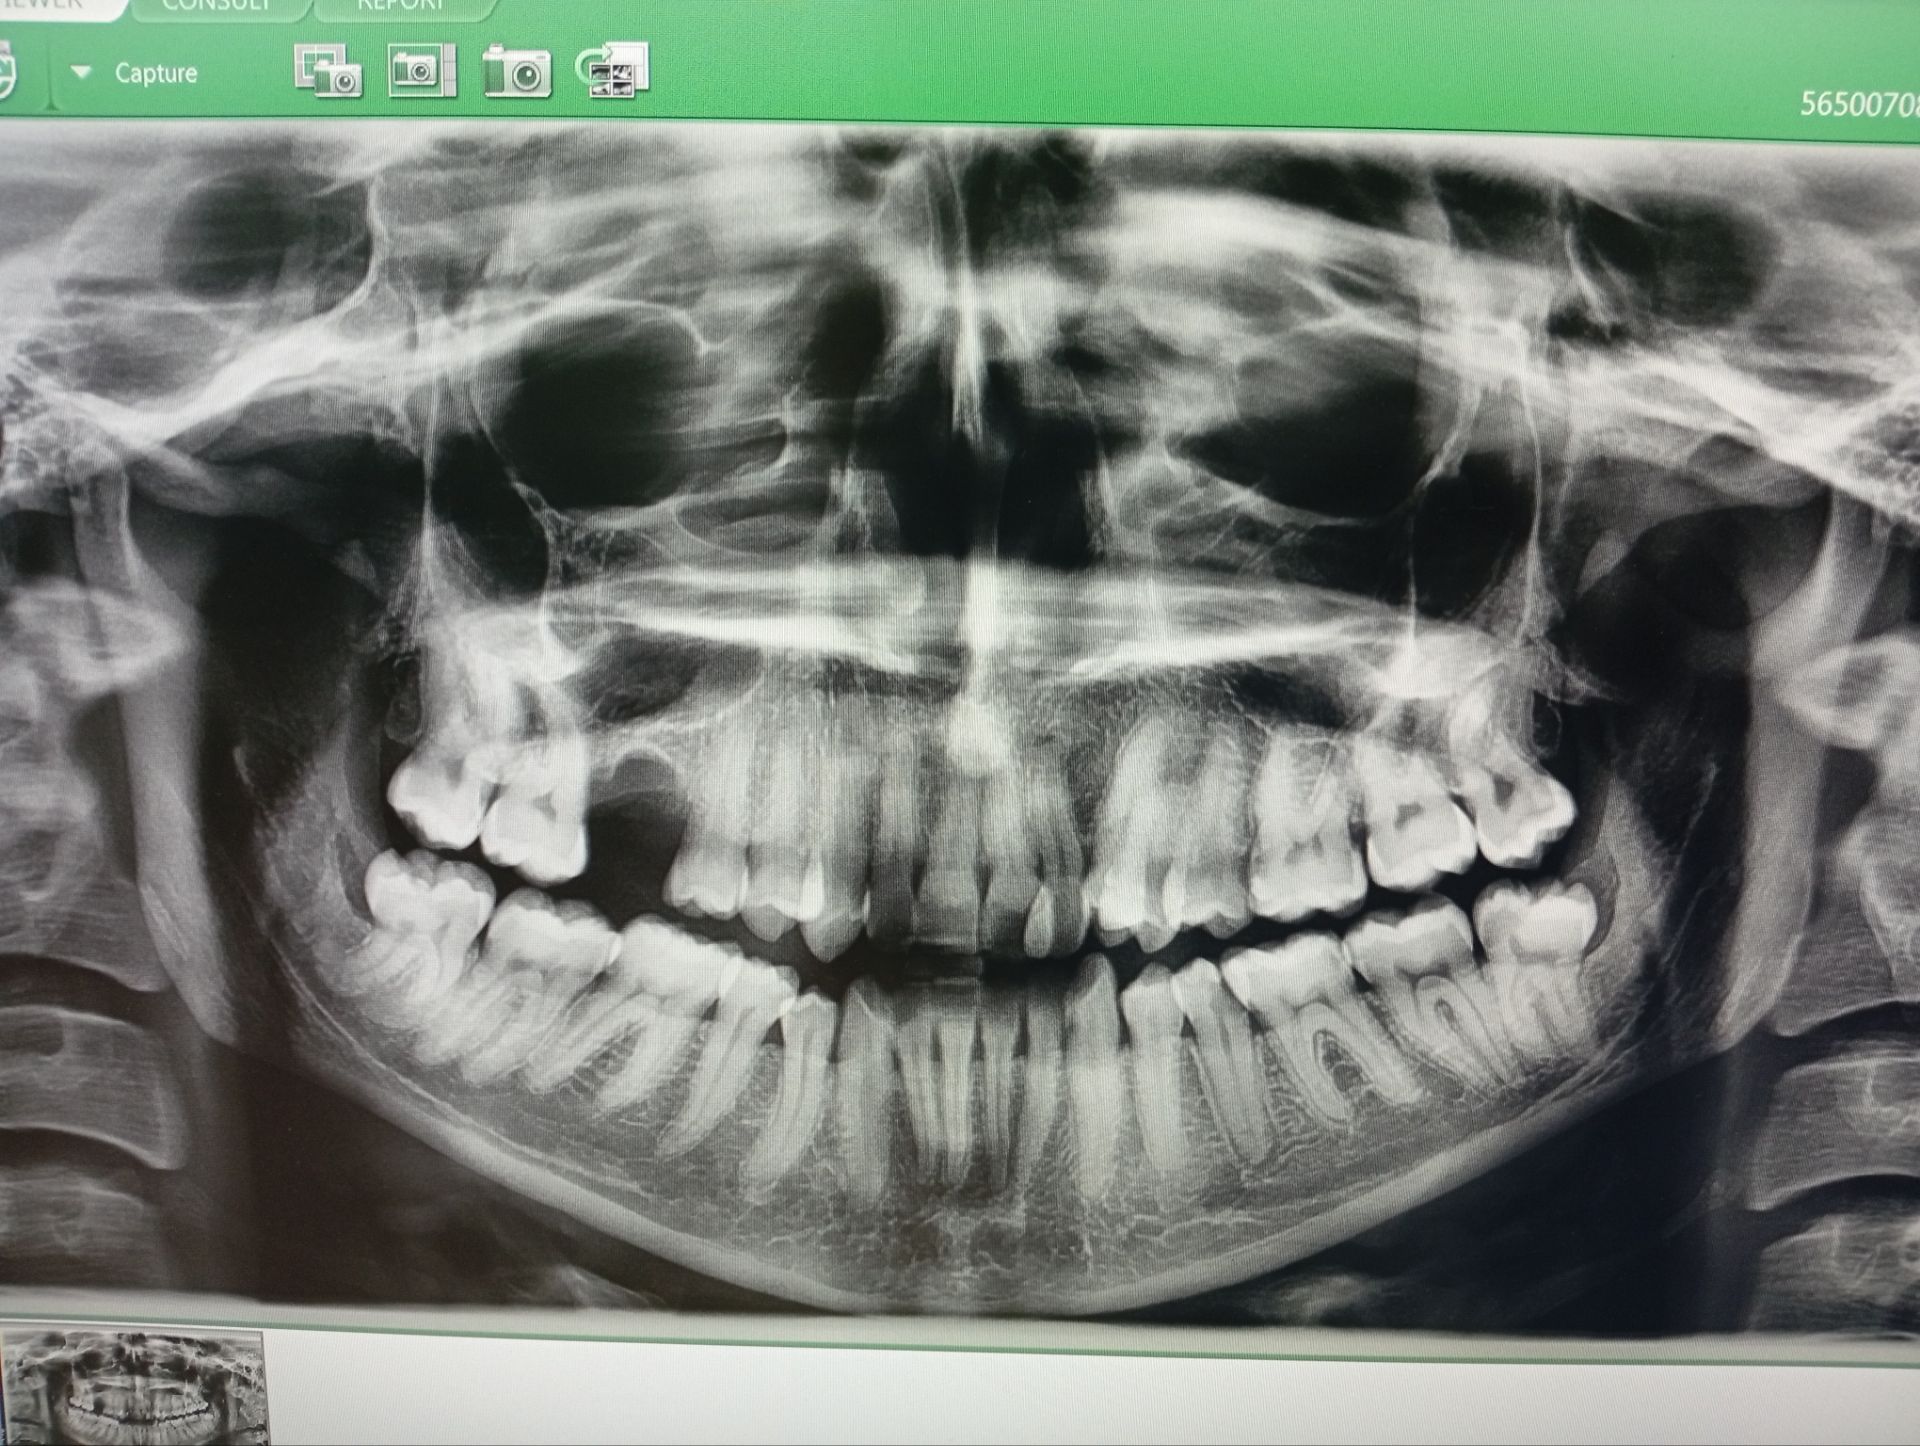

اون ک گفت سه تا عصب کشی

نه اصلا

به جز همونی که عصب کشی کردی هیچ کدوم نیازی به عصب کشی ندارن

واضحا دو تا پوسیدگی سطحی میبینم که ترمیم میخواد

یکی دو تا هم هست که مشکوکه و معاینه میخواد

پوسیده باشه فقط ترمیم نیازه